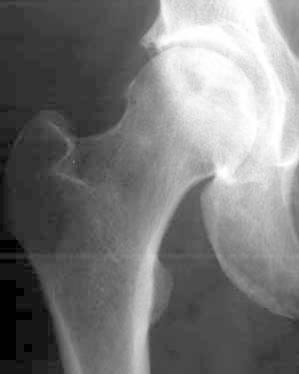

Avascular necrosis of the femoral head (AVN) is an increasingly common cause of musculoskeletal disability, and it poses a major diagnostic and therapeutic challenge. Although patients are initially asymptomatic, AVN usually progresses to joint destruction, requiring total hip replacement, usually before the fifth decade. Avascular necrosis is characterized by osseous cell death due to vascular compromise. Avascular necrosis of bone results generally from corticosteroid use, trauma, pancreatitis, alcoholism, radiation, sickle cell disease, infiltrative diseases (e.g. Gaucher's disease), and Caisson disease. The most commonly affected site is the femoral head and patients usually present with hip and referred knee pain. The aim of diagnostic imaging procedures in avascular femoral head necrosis is to provide the patient with a stage-adapted therapy. Therefore, a differentiated diagnostic work-up is needed. Native radiography of the hip in two planes is still the first step. Over the past years, the diagnosis of femoral head necrosis has experienced tremendous improvement due to the use of MRI and CT scans. Because of these improvements the correct stage can be diagnosed early and the appropriate therapy can be initiated immediately. Today, MRI is the most sensitive diagnostic imaging procedure. CT scans can be particularly useful to exclude subchondral fractures. The use of bone scintigraphy is restricted to exceptional cases. In Europe, the ARCO classification of avascular femoral head necrosis has been widely accepted. In this overview, we describe the specific characteristics of the different diagnostic imaging procedures and illustrate them with appropriate imaging material.

股骨头缺血性坏死(AVN)是导致肌肉骨骼残疾的一个日益常见的原因,它带来了重大的诊断和治疗挑战。尽管患者最初没有症状,但AVN通常会发展为关节破坏,通常在50岁之前就需要进行全髋关节置换。缺血性坏死的特征是由于血管受损导致骨细胞死亡。骨缺血性坏死通常由使用皮质类固醇、创伤、胰腺炎、酗酒、辐射、镰状细胞病、浸润性疾病(如戈谢病)和减压病引起。最常受累的部位是股骨头,患者通常表现为髋部疼痛并伴有膝关节牵涉痛。股骨头缺血性坏死诊断成像程序的目的是为患者提供适合其分期的治疗。因此,需要进行差异化的诊断检查。髋关节的双平面X线平片仍然是第一步。在过去几年中,由于使用了MRI和CT扫描,股骨头坏死的诊断有了巨大改善。由于这些改进,可以早期诊断出正确的分期,并立即开始适当的治疗。如今,MRI是最敏感的诊断成像程序。CT扫描对于排除软骨下骨折特别有用。骨闪烁显像的应用仅限于特殊情况。在欧洲,股骨头缺血性坏死的ARCO分类已被广泛接受。在本综述中,我们描述了不同诊断成像程序的具体特征,并用适当的影像资料进行说明。